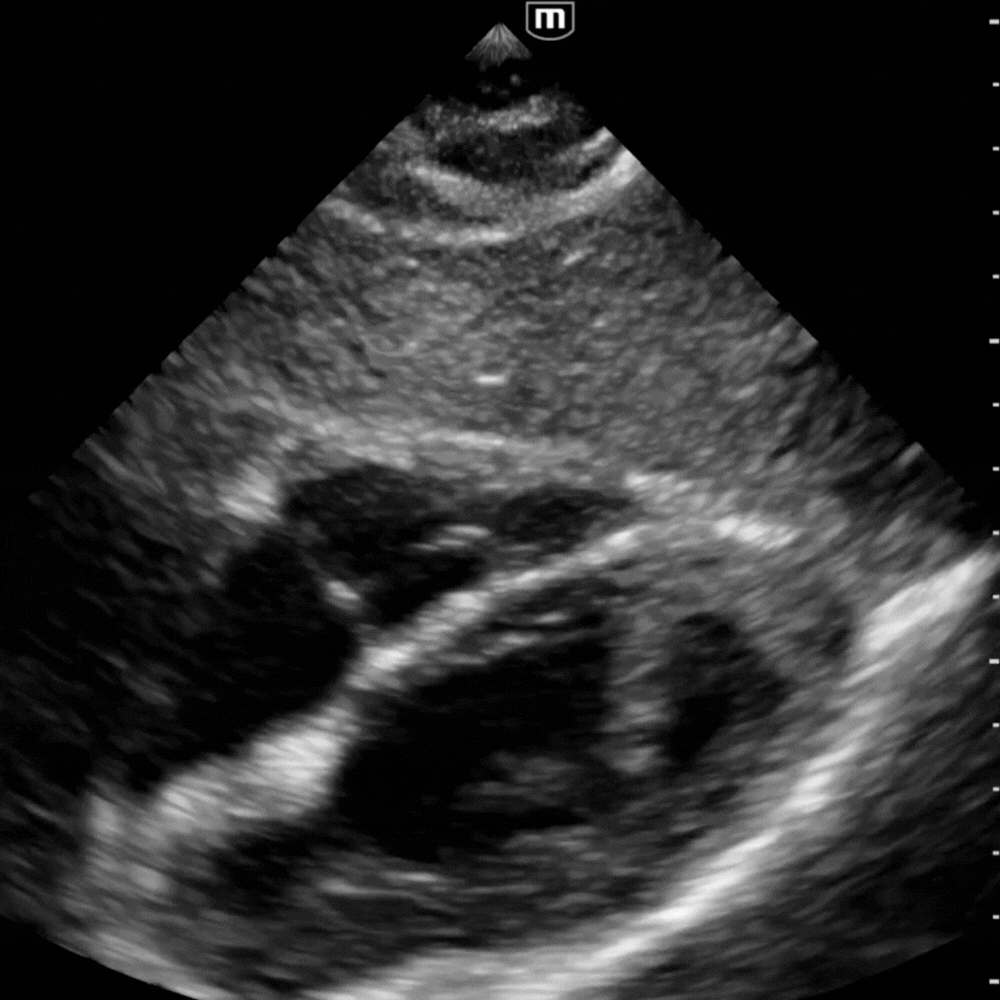

![]()

Boucle sous costale avec rapport VG/VD normal